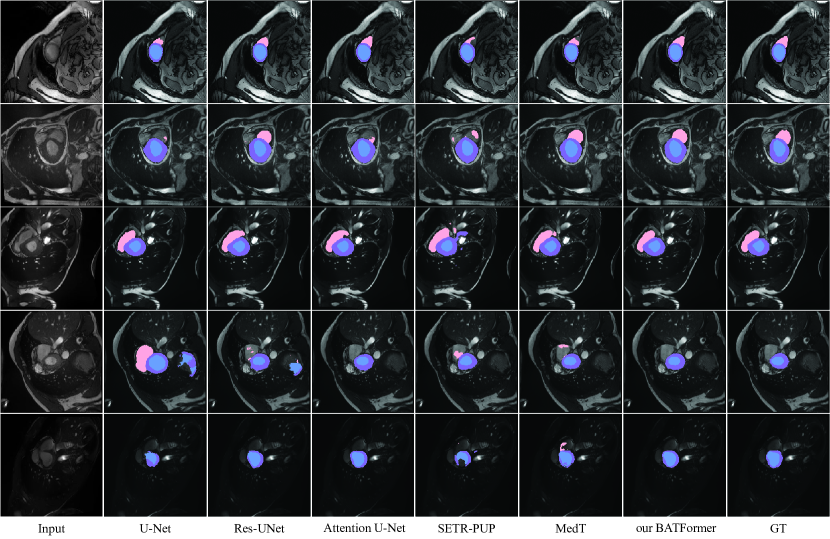

Refer to caption

Figure 5: Qualitative comparison results on the ACDC dataset. From left to right: the raw images, the segmentation maps produced by U-Net [1], Res-UNet [2], Attention U-Net [3], SETR-PUP [9], MedT [16], and our BATFormer respectively, and the manual annotations. The pink, purple, and blue regions denote the right ventricle, the myocardium, and the left ventricle respectively.

4.3.3 Qualitative Results

Qualitative segmentation results of different methods on the ACDC dataset are presented in Fig. 5. Suffering from local contextual similarity, CNN-based methods produce more false positives. Comparatively, transformer-based methods produce extensive false negatives with distorted boundaries due to rigid partitioning. Thanks to both CGT and BLT, BATFormer achieves the best segmentation performance, especially on boundary consistency with manual annotations.